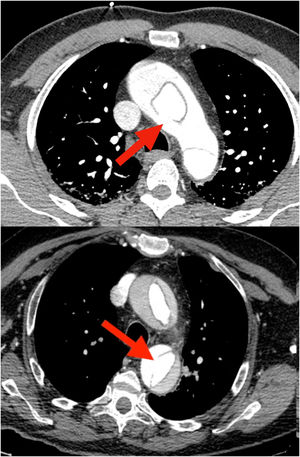

Probablemente la única situación en la que sea imprescindible para salvar la vida del paciente es cuando la falsa luz esté rota a nivel del arco, situación poco frecuente (figs. 1 y 2). Más frecuente es la presencia de malperfusión cerebral estática (por disección de uno o varios de los troncos supraaórticos, con oclusión de la luz verdadera) o de malperfusión visceral dinámica (por colapso de la luz verdadera, generalmente por reentradas en el arco o en la aorta descendente proximal). En estas dos circunstancias, aunque no es mandatorio, la sustitución del arco aórtico sí es la manera más eficaz de corregir la malperfusión20 (figs. 3 y 4).